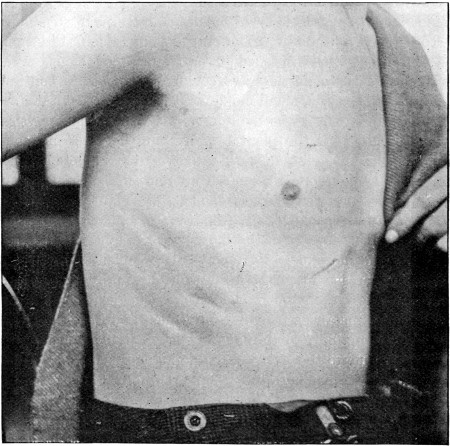

81. Superficial Track in Anterior Body-wall 377

84. Subcutaneous Division of Abdominal Muscles409